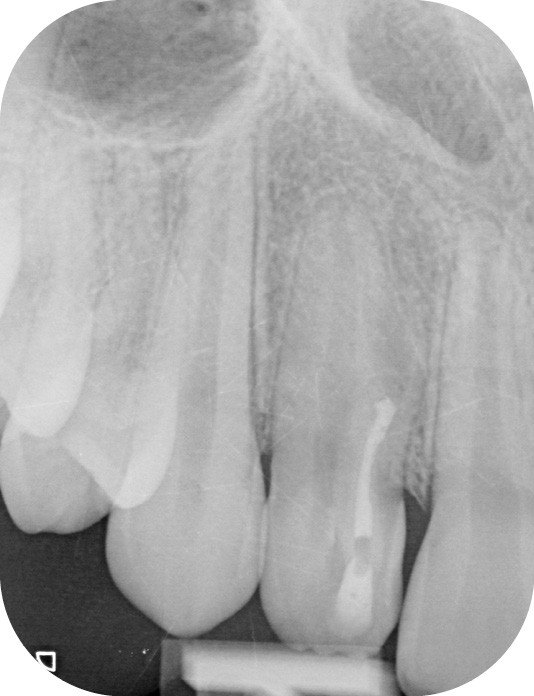

Lors du traitement endodontique, un suintement important étant encore présent à la fin de la seconde séance. J’ai pris la décision d’irriguer la crypte osseuse et sa lésion à travers la fistule à l’aide d’iso-bétadine délivrée par une aiguille stérile. C’est par empirisme que je réalise cette manœuvre ayant déjà montré à chaque reprise des résultats cliniques positifs. C’est l’équivalent d’une décompression sans tous les désavantages de cette dernière (fig. 4 et 5).

Lors de la séance d’obturation, le canal étant sec malgré la persistance de la fistule, j’ai réalisé l’obturation radiculaire et coronaire. L’obturation radiculaire a été réalisée à l’aide d’un ciment biocéramique en technique du single cône coupé et foulé à l’entrée canalaire (fig. 6).